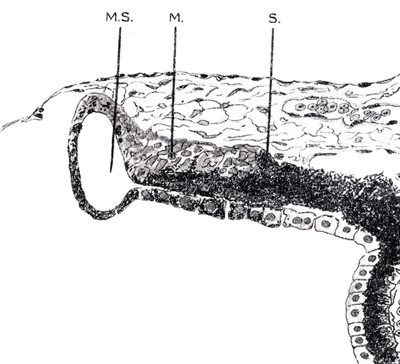

B - MS, M, S. detalle a mayor aumento.

Foto tomada de: Ida Mann ; The development of the Human Eye. 1969. Grune & Straton Inc N.Y

El Sphinter pupillae inicia su aparición alrededor del 4º mes de la gestación, cuando en el protoplasma de las células cúbicas de la capa anterior, en el extremo del borde iridiano del Seno Marginal aparecen trazas de fibrillas; con el tiempo se desplazan levemente hacia atrás dejando el borde libre y se demarcan claramente de sus células germinales, ya que éstas tardíamente adquieren pigmentación y las células musculares nunca se pigmentan. El esfínter queda levemente sumergido dentro de la sustancia de la parte pigmentada del iris y su límite posterior queda marcado por una cresta conocida como la cresta o espolón de Michel (Michel’s Spur).

A los 6 meses aparecen derivados mesodérmicos en forma de fibrillas que contienen capilares que invaden los haces musculares y que finalmente lo separan completamente del ectodermo paternal. El Sphinter Pupillae esta prácticamente completo al 8avo mes.